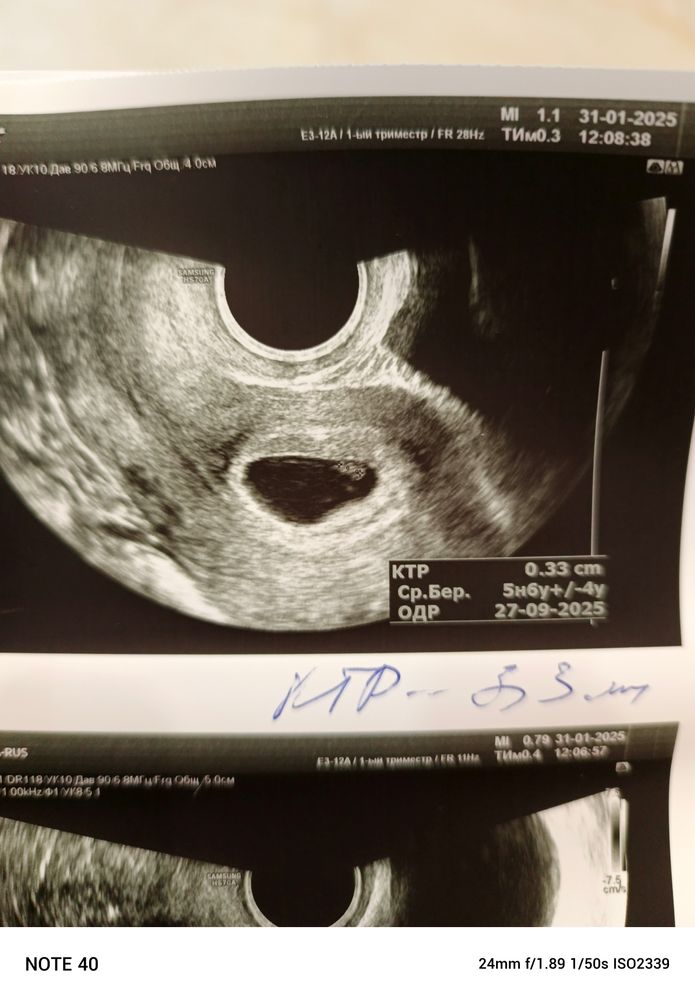

Это ведь не большая отслойка, да?